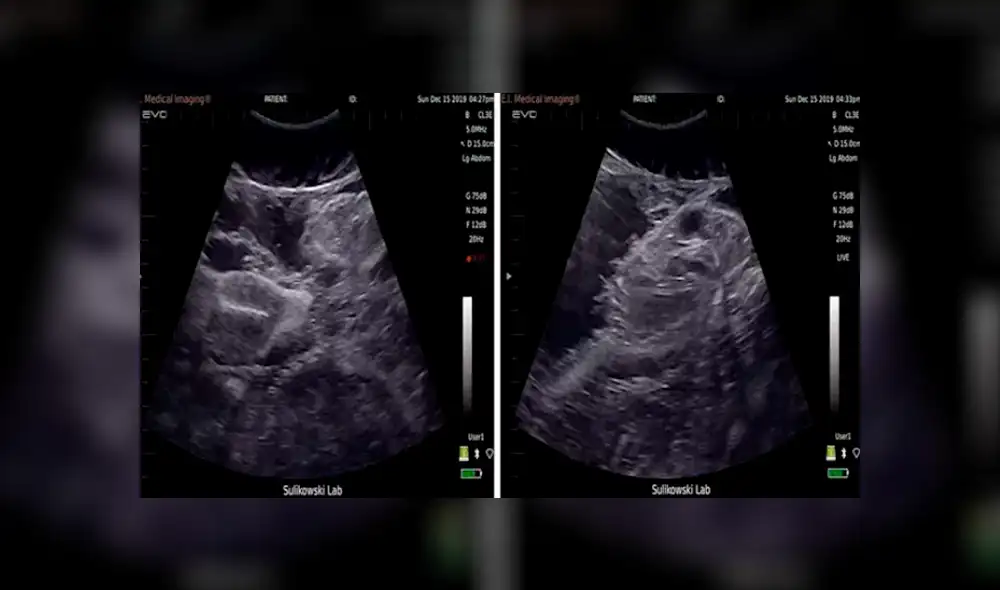

Nada más asombroso que la propia naturaleza. A través de un impactante video, que se ha hecho viral en Facebook y YouTube, un grupo de científicos difundió las imágenes del ultrasonido realizado a un tiburón, que muestra a uno de sus fetos moviéndose dentro del útero.

Las imágenes, que han causado conmoción en Facebook y YouTube, y que ya han dado la vuelta al mundo, revelan los singulares movimientos que realiza un tiburón tigre bebé antes de nacer.

En la grabación, se observa los rápidos movimientos que realiza el tiburón bebé dentro de la panza de su madre. Una peculiar imagen que muchos la han asemejado con la de una ecografía humana.

El insólito video fue registrado en una playa de las Bahamas, como parte de un proyecto de un grupo de científicos que estudia la conservación de tiburones.

Según indicaron los autores del video viral de Facebook, pudieron captar las imágenes usando tecnología de punta, tras lograr escanear a cinco tiburones dentro del agua. Pero, ¿cómo lo hicieron?

Tras navegar hasta Tiger Shark Bay, en las Bahamas, los científicos sostuvieron al tiburón cerca de su bote con ayuda de correas. Inmediatamente, el doctor Sulikowski usó su ultrasonido portátil para hacer la ecografía mientras analizaba simultáneamente los resultados en auriculares de realidad virtual.

La inusual grabación del feto de tiburón retorciéndose dentro del útero de su madre no tardó en hacerse tendencia en las redes, generando diversas reacciones y comentarios por parte de los usuarios de Facebook y YouTube, quienes compartieron las imágenes destacando lo sorprendente que pueden llegar a ser los misterios de la naturaleza, de los que podemos ser testigos gracias a la tecnología.